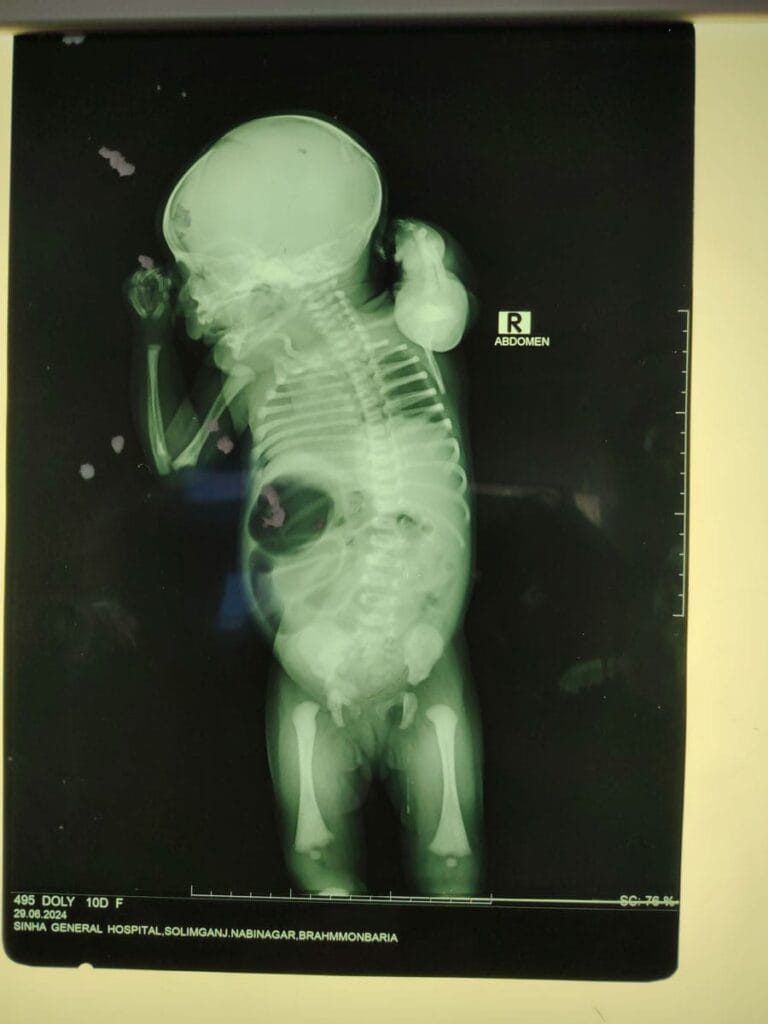

Neonatal Surgery

Neonatal surgery is the most delicate super specialty of pediatric surgery. Neonate means the babies 1-28 days after birth. These tiny babies are completely different from adults. They are small, fragile, and more prone to infections and other complications. Surgery on these tiny babies, therefore, requires skill and experience to deal with the delicate small structures. The pre and post-operative treatment of these babies are also critical and contribute to the outcome.

Neonatal surgical conditions are mainly congenital (present from birth) but acquired conditions are also there.

Common congenital neonatal surgical conditions:

- Esophageal atresia

- Diaphragmatic hernia

- Neonatal intestinal obstruction from different causes

- Volvulus neonatorum

- Anorectal malformations

- Abdominal wall defects- omphalocele, gastroschisis, dystrophy bladder.

- Patent VID/Urechus

- Spina bifida with meningocele/ myelomeningocele

- Sacrococcygeal teratoma